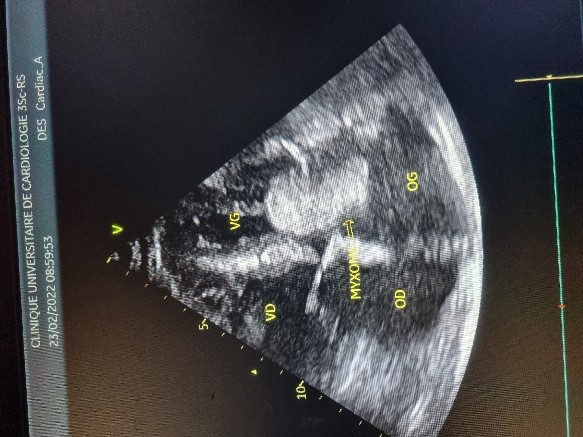

L’électrocardiogramme notait un rythme sinusal régulier avec une fréquence cardiaque à 83 bpm, des anomalies de la repolarisation en antéro septal à type d’ondes T biphasiques et en inférieur à type d’ondes T négatives asymétriques. La biologie était normale. L’échocardiographie (transthoracique et transœsophagienne) retrouvait les mêmes caractéristiques avec une masse appendue à la face atriale de la grande valve mitrale, obstruant partiellement l’orifice mitral et mesurant 49mm ×27 mm. Elle faisait protrusion dans le ventricule gauche en diastole (Figures 5 et 6). Cette masse était évocatrice d’un myxome de l’oreillette gauche. Le ventricule gauche n’était pas dilaté (DTDVG= 46mm), avec une fraction d’éjection systolique à 74% au Simpson biplan. Les pressions de remplissage du ventricule gauche étaient élevées. L’oreillette gauche était dilatée (VOG= 43mL/m²). Les cavités droites n’étaient pas dilatées. La fonction ventriculaire droite était normale (TAPSE= 24mm). On notait une hypertension pulmonaire avec PAPS =75mmHg, VmaxIT= 4,18 m/s. La veine cave inférieure était fine et compliante.

Figure 4 (a et b): Echocardiographie transoesophagienne en bi dimensionnelle, incidence 4 cavités plan oblique à 135° montrant un myxome appendu au septum inter atrial (Cas clinique n°2). VG= ventricule gauche ; OG= oreillette gauche ; VD= ventricule droit.